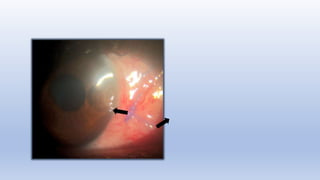

Mrs xxx Devi – seen on 23.4.22

Peripheral Epithelial defect Associated with vascularization and anterior uvitis